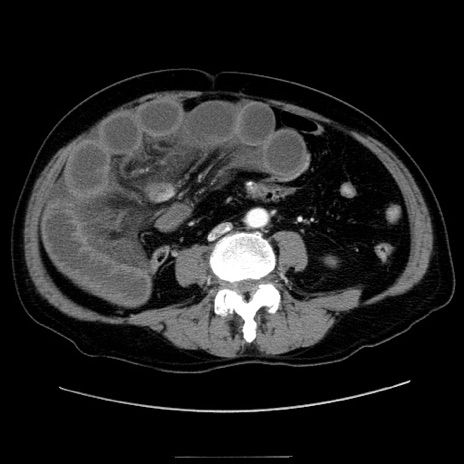

症例30(横断像)

【症例】80歳代男性

【主訴】臍周囲痛

【現病歴】約6時間前から臍下部痛が出現。次第に腹部膨隆・背部痛も生じてきたため来院。背部痛の場所は変化しない。

【既往歴】腎盂腎炎

【身体所見】意識清明、BT 36.3℃、BP  131/87mmHg、P 87bpm、SpO2 100%(RA)、臍周囲自発痛・圧痛あり、反跳痛なし、自発痛部位に一致して板状硬あり、腹部膨隆、腸雑音減弱、CVA tenderness両側陰性。

【データ】WBC 19600、CRP 0.33